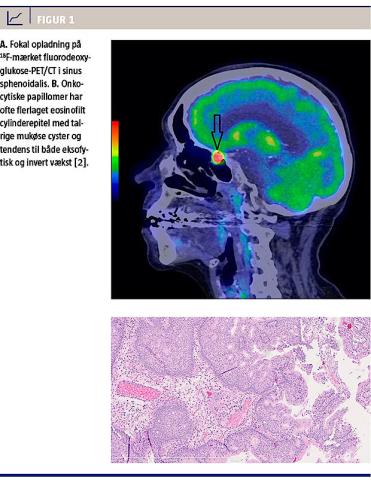

18F-mærket fluorodeoxyglukose (18F-FDG)-PET/CT benyttes som et vigtigt redskab i diagnosticering og staging af hoved-hals-cancer [1]. I den her omtalte sygehistorie gav kraftig fokal 18F-FDG-opladning anledning til et hurtigt afklarende indgreb på mistanke om metakron hoved-hals-cancer, men en histopatologisk undersøgelse viste benignt papillom.

En 77-årig kvinde, som i 1992 blev mastektomeret på venstre side pga. mammacancer, henvendte sig hos egen læge pga. hævelse på venstre side af halsen. Egen læge henviste til CT af hals, thorax og øvre abdomen, og denne skanning viste multiple lymfeknuder omkring venstre klavikel. Patienten blev henvist i kræftpakkeforløb til en øre-, næse- og halsafdeling. Objektivt fandt man ved palpation og UL-undersøgelse forstørrede lymfeknuder i level V på venstre side. Der blev bestilt en 18F-FDG-PET/CT og taget finnålsaspirat. Sidstnævnte viste, at det drejede sig om metastase fra et adenokarcinom udgående fra mammae. 18F-FDG-PET/CT viste opladning i de beskrevne lymfeknuder i level V på venstre side med standardized uptake value (SUV) maks. på 3,6 g/ml. Som bifund blev der fundet højt 18F-FDG-optag (SUV maks. 16,4 g/ml) i en lille polypøs forandring, der målte 8,3 mm × 5,9 mm, i sinus sphenoidalis på venstre side (Figur 1A). Patienten havde hverken øre-, næse-, halsgener eller oftalmologisk relaterede gener. CT’en viste ingen knogledestruktion i området, og der var ikke mistanke om malign forandring. Bifundet blev konfereret med onkologerne, og de ønskede polyppen biopteret for at udelukke metakron cancer. Der blev foretaget et functional endoscopic sinus surgery-indgreb mhp. bioptering af den polypøse forandring. Forandringen blev peroperativt beskrevet som benign af udseende og lignede mest af alt et mucocele/en benign polyp. Endeligt histologisvar viste papillom med onkocytisk præg (Figur 1B) uden tegn til malignitet.

Den histopatologiske beskrivelse i sygehistorien rejser mistanke om papillomatøs tumor med onkocytisk præg (Figur 1B). Den manglende invasive vækst set på CT og de manglende symptomer kunne tale for en benign forandring. Da sinus sphenoidalis ikke er et oplagt metastaseringsområde for mammacancer, fandt man det ligeledes lidet sandsynligt, at det drejede sig om metastase. 18F-FDG-opladningen var dog så kraftig, at den i sig selv gav mistanke om malign forandring og derfor henledte tanken på

metakron hoved-hals-cancer.